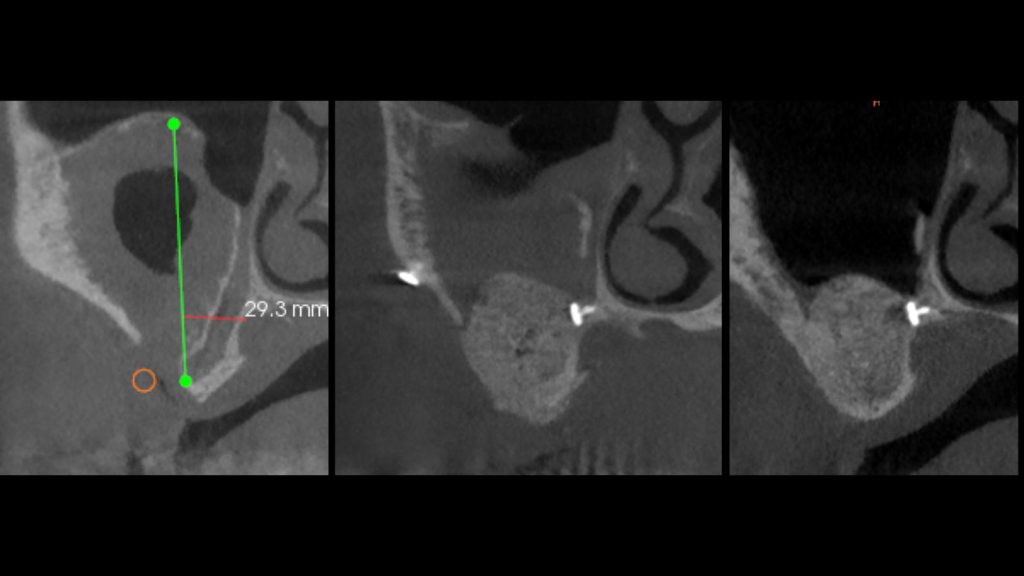

- Lecture clinique et radiologique (panoramique, CBCT : bases de lecture)

- Identifier un déficit osseux nécessitant une ROG

- Notions de volume, stabilité et espace de régénération